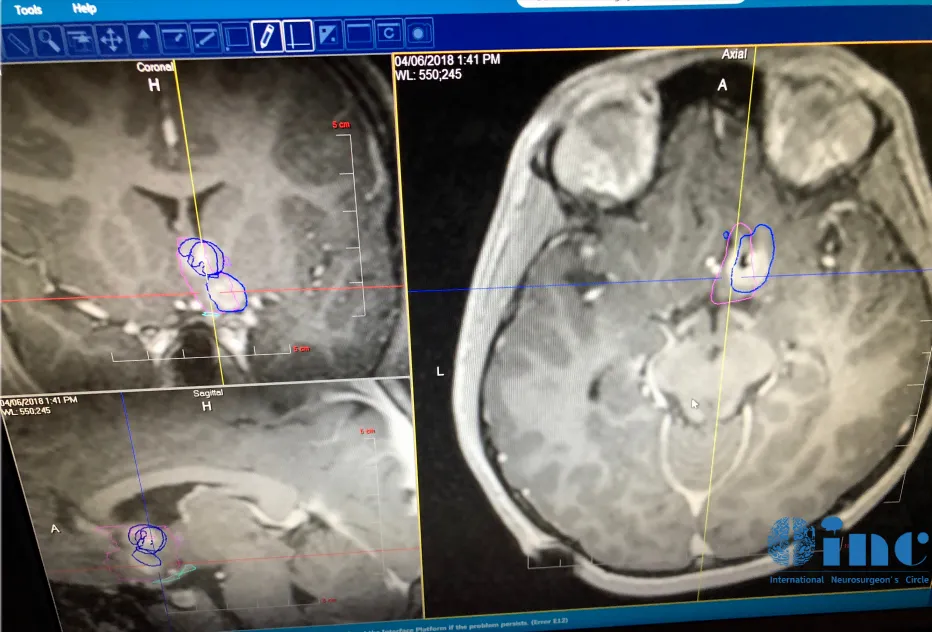

然而他们担心开颅手术会造成并发症,而且孩子年纪较小,术后护理难度更大。在多方打听后他们找到了INC加拿大Rutka教授,决定咨询教授是否有不开颅就能消融俊俊下丘脑错构瘤的办法。Rutka教授回复可以为俊俊实行LITT消融病灶。

Rutka教授及其团队做了非常充分的准备,LITT利用的是先进的磁共振成像MRI引导技术,可以清晰地识别病灶与周围健康脑组织的位置关系,进而制定精确的手术路径。

Rutka教授及团队LITT手术准备中

手术在俊俊头部皮肤上切一个约2-4毫米宽的小切口,之后在其中插入激光光纤探头,将探头引导到病灶目标所在的位置,利用脉冲激光消融或烧掉肿瘤组织即可。在教授和其团队成员的努力下,俊俊的病变得到了很大程度的消融。

按照手术方案设定手术入路轨迹后,插入激光探针准备消融